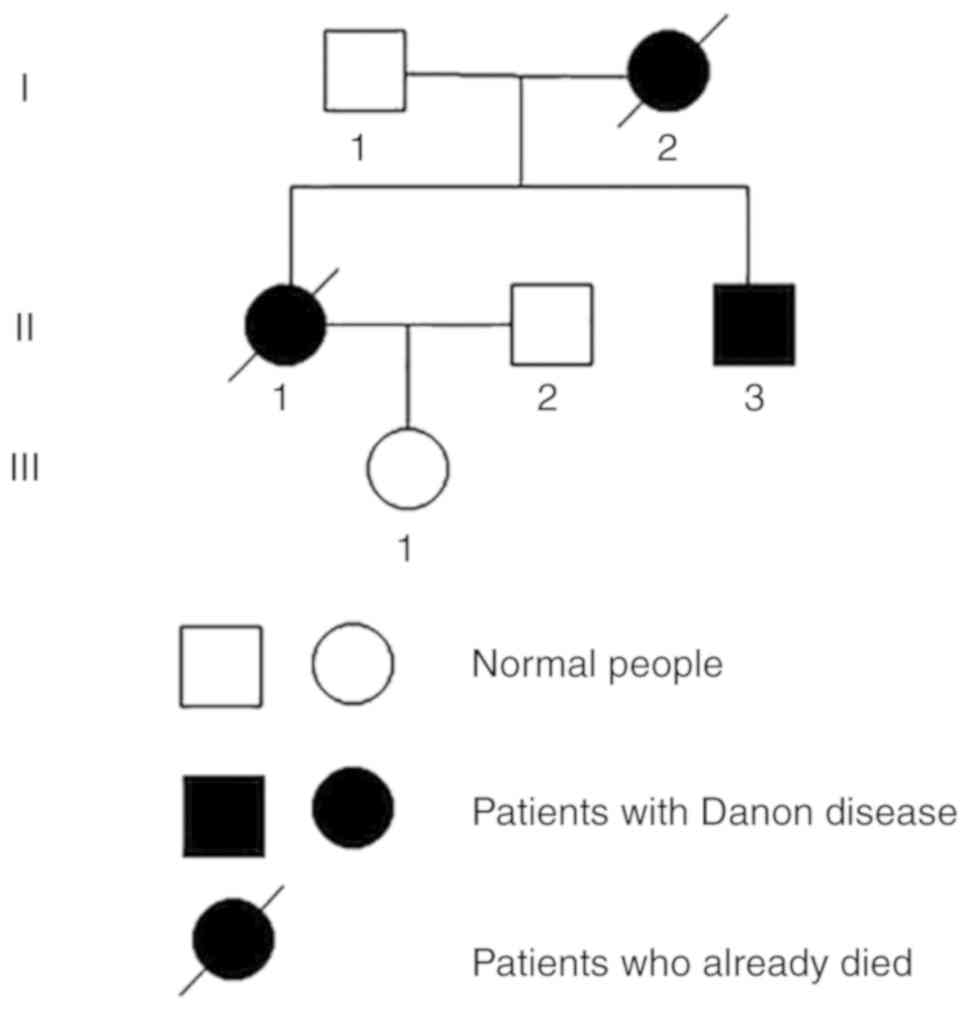

Danon disease is an inherited disease that may be

passed on to the next generation. The present study reports on two

cases of Danon disease in a single family with distinctly different

phenotypes. In this pedigree, three generations involving 6 family

members were assessed, including one case of sudden death (Patient

I:2), and two cases of cardiomyopathy (Patients II.1 and II.3).

Other family members

Patients I.1 and III.1 had normal psychomotor

development and no exercise intolerance. The LAMP2 gene mutation

was not identified in these two family members. Patient I.2, the

mother of Patient II.1, suffered a sudden cardiac death without an

accurate diagnosis. Patient II.2 was normal with no sign of mental

or physical disorders.